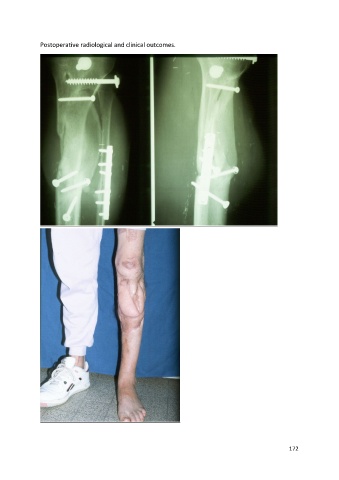

Postoperative radiological and clinical outcomes.